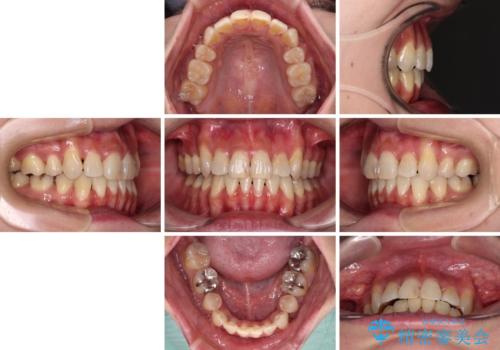

ハーフリンガルでの矯正治療は、表側矯正よりも期間がかかることが多く、抜歯矯正では3年以上かかることも珍しくありません。

デコボコが強い一方で出っ歯ではなかったため、抜歯したスペースを容易に閉じることができ、短期間での治療となりました。